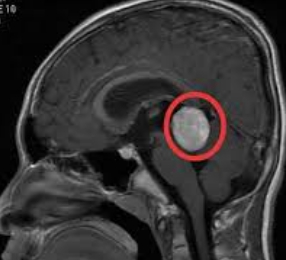

8岁男孩,在国内被查出松果体区肿瘤,为更好的治疗,在INC国际神经外科医生集团的帮助下,赴德治疗。国际颅底肿瘤手术教授巴特朗菲教授为其进行了手术,教授取幕下小脑上入路结合幕上枕下乙状窦旁经小脑幕入路,实施肿瘤全切除。术后一天患者清醒,术后ICU观察两天,术后一般情况好,无明显并发症,顺利出院。

手术前后影像资料对比